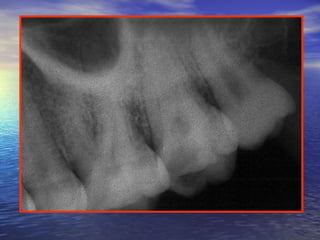

The teeth which are commonly related toThe teeth which are commonly related to

the sinus arethe sinus are most oftenmost often thethe max. molarmax. molar

rootsroots,, less frequentlyless frequently thethe premolarspremolars andand

rarelyrarely thethe canine rootscanine roots ..

Note:

In the deciduous teeth the related teeth are the max.

first and second molars – rarely the canine.

Relationship of the floor of the sinus to the roots of theRelationship of the floor of the sinus to the roots of the

maxillary teethmaxillary teeth